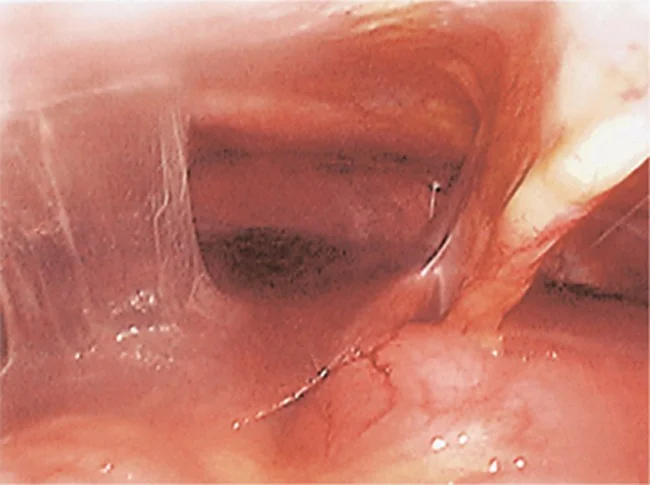

Fitz-Hugh–Curtis Syndrome

Fitz-Hugh–Curtis syndrome showing perihepatic adhesions (typical violin string appearance).